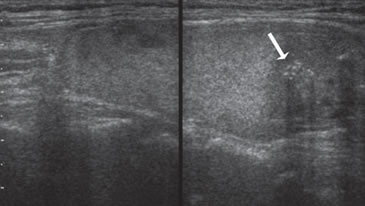

Figura 24. Comparación entre un nódulo coloideo de aspecto espongiforme

(flecha abierta) con un carcinoma papilar (flecha) hipoecogénico

de bordes infiltrativos con micro y macrocalcificaciones,

de forma más alta que ancha.